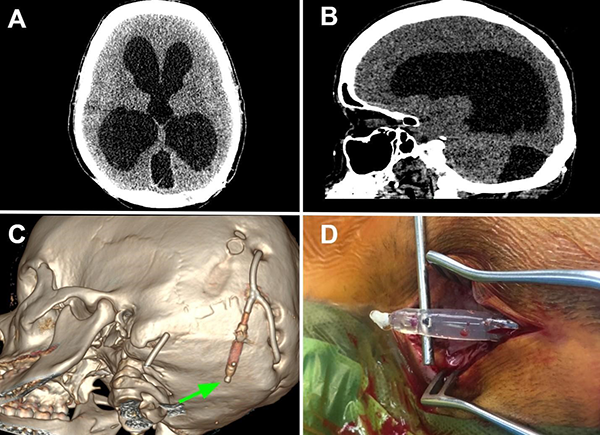

Tras 2 meses, la paciente volvió a consultar en guardia por náuseas, cefalea bifrontal con irradiación holocraneana de intensidad moderada y vómitos. Al examen físico se constató limitación de la mirada superior y colección líquida sobre herida craneal de derivación. Se realizó TC de cerebro con evidencia de ventriculomegalia y desconexión de catéter distal a la válvula (Figura 1). El estudio radiográfico reveló migración caudal del segmento distal del catéter al corazón (Figura 2). El segmento migrado fue rescatado mediante un abordaje endovascular transfemoral, en el cual se enroscó el catéter migrado con un catéter pigtail y se lo desplazó hasta la vena ilíaca primitiva izquierda para luego ser capturado a nivel ilíaco con un lazo trilobulado (Figura 3).

Figura 1. A y B. Corte axial y sagital de TC de cerebro evidenciando marcada hidrocefalia supratentorial. C. Reconstrucción 3D de dicha tomografía, se observa desconexión del catéter distal (flecha verde). Aclaración: sobre mastoides izquierda se evidencia catéter calcificado de válvula previa abandonada. D. Imagen intraquirúrgica con evidencia de desconexión de segmento distal.